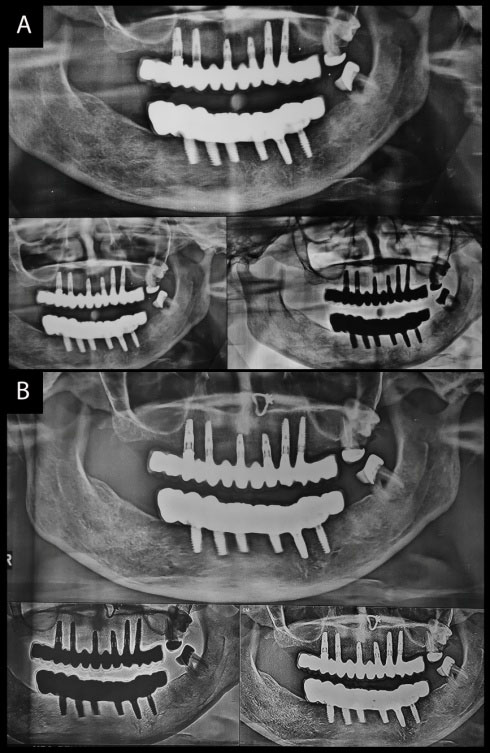

Attachment loss around teeth in the partially edentulous patient increased further to around 3.5-4 mm. There was no implant loss, prosthesis complications like ceramic fracture and unscrewing of abutments in both patients (Figures 9 and 10).This could be attributed to follow-ups at regular intervals.

japid-11-39-g009

Figure 9. 10-year follow-up for the completely edentulous patient.

japid-11-39-g010

Figure 10. Follow-up for the partially edentulous patient.